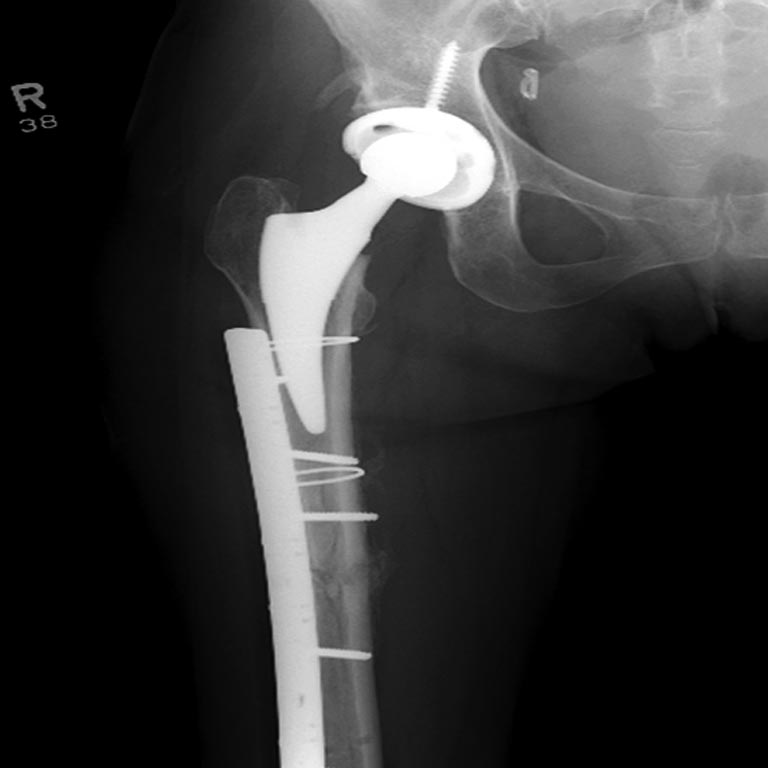

На 25 день с момента травмы операция на Jackson table с боковым обширным

доступом. Удаление стержней с местной обработкой. В тазобедренном

суставе удаление головки, на дне вертлужной впадины полная отслойка

хряща. Вертлужный компонент с одним винтом и короткая ножка -  Fitmore

press fit stem. На второй день однократно доза радиации для профилактики

гетеретопической оссификации.  Послеоперационный период без температуры.

Выписана. Нагрузку разрешили на левой стороне, а полная в 3 мес.  Здесь

снимки при амбулаторном наблюдении​: послеоперационно, 2 мес, 3 мес и 6

мес. Нагрузка полная, отсутствует хромота, и нет жалоб.